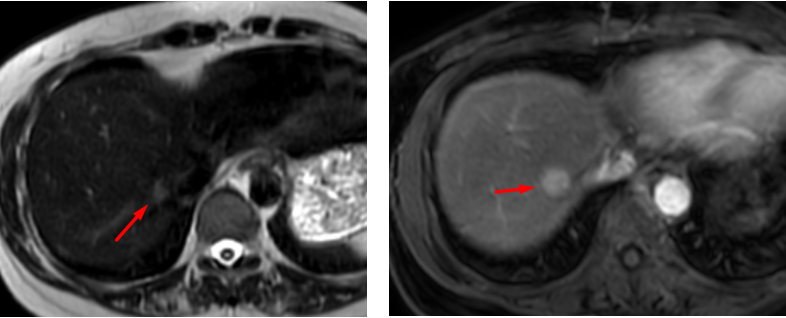

Hình ảnh tổn thương gan không rõ bản chất khi chụp MRI thường

Hình ảnh tổn thương gan giữ thuốc đối quang từ đặc hiệu tế bào gan thì gan mật, gợi ý tính chất của tăng sản thể nốt khu trú (FNH)